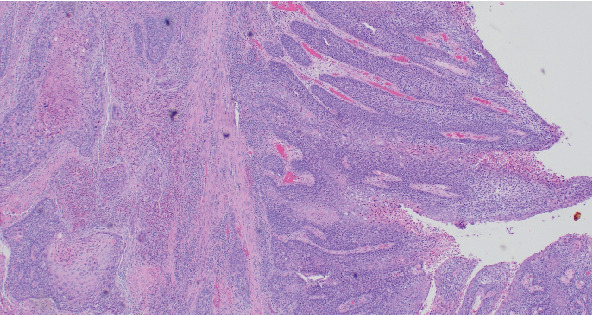

原发性子宫内膜鳞状细胞癌(PESCC)是一种罕见的病理。有关诊断和治疗的数据有限,完全基于病例报告和系列。我们报告一个独特的情况下,绝经后妇女的历史,艾滋病毒和肛门癌s/p放射治疗8年前。患者的首发诊断是有恶臭的阴道分泌物,抗生素难治性。尽管进行了广泛的检查,但患者自出现症状以来诊断明显延迟,但最终通过妇科肿瘤手术分期诊断为IB期PESCC。尽管她有肛门癌病史,并接受过不完整的盆腔放疗,但在肿瘤委员会上讨论了该病例,并认为该患者可以接受外束放疗。在我们的报告中,我们详细讨论了患者的表现、病程和治疗,并回顾了文献。

Primary endometrial squamous cell carcinoma (PESCC) is a rare pathology. Data regarding diagnosis and treatment is limited and is solely based on case reports and series. We report a unique case of a postmenopausal woman with a history of HIV and anal cancer s/p radiation therapy 8 years prior. The patient's presenting diagnosis was malodorous vaginal discharge refractory to antibiotics. The patient had a significant delay in diagnosis since the onset of symptoms despite extensive workup but eventually underwent surgical staging by gynecologic oncology with a diagnosis of Stage IB PESCC. Despite her reported history of anal cancer for which she received an incomplete course of pelvic radiation, the case was discussed at tumor board and the patient was deemed a candidate for external beam radiation therapy. In our report, we discuss, in detail, the patient's presentation, course, and treatment and review the literature.